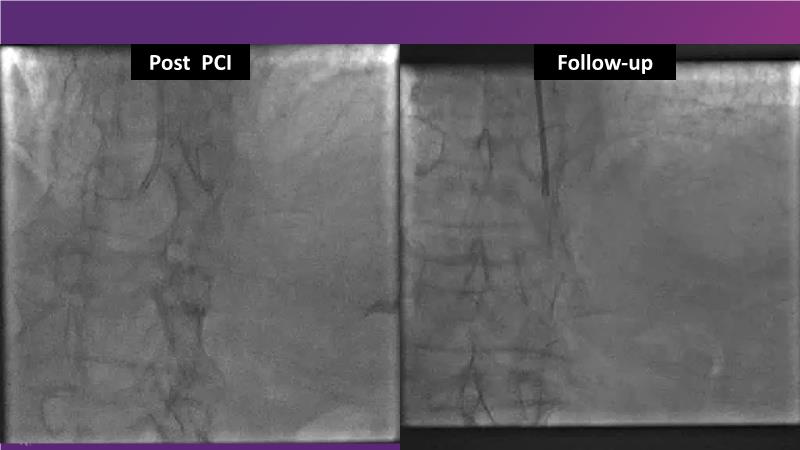

Consult this session to understand the technology and scientific evidence of the novel sirolimus drug-coated balloon, to learn its utility for PCI in a variety of lesion and patient subsets and to understand the evidence and outcomes in real-world patients.

- To learn the utility of the DCB for PCI in a variety of lesion and patient subsets

- To understand the evidence and outcomes of this DCB in real world patients